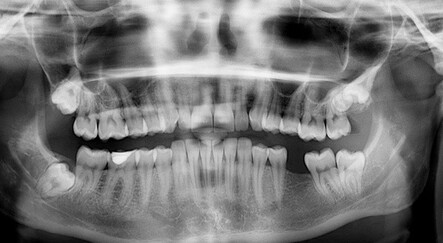

Dikkat, kilo almanızın sebebi çürük dişleriniz olabilir!

Çürük dişleriniz sadece ağzınıza değil, vücudunuzdaki birçok organa zarar veriyor. Çünkü çürük dişlerin yapısında bulunan mikroorganizmalar ve oluşturdukları lezyonlar hem kalbe hem böbreklere hem de mideye zararlı. Ayrıca çürük dişler fazla kilo almanıza da yol açabiliyor. Nasıl mı? Gelin, cevabını uzmanından dinleyelim…

Çürük dişten ağız içindeki iltihaplara kadar farklı durumlar, kilo almamıza yol açabiliyor. Diş Hekimi-Protez Uzmanı Hatice Ağan, fazla kilo almamızın ya da obezitenin ağız ve diş sağlığı ile yakından ilişkisi olduğunu belirterek önemli bilgiler verdi.

Obezitenin ağız ve diş sağlığı ile ilgili olumsuz etkileri mevcut. Yapılan çalışmalarda obez hastalarda diş çürükleri ve gingivitis dediğimiz diş eti hastalıklarında belirgin artış gözlenmiştir. Bunlara bağlı olarak bu kişilerde ağız kokusu da gelişebilir. Yine obezlerde görülen reflüye bağlı, ağız içi asiditesinin artması da dişlerdeki mine erozyonu ve aşınmalarını arttırıyor, diş hassasiyetleri oluşabiliyor. Bu kişilerde ağız kuruluğunda artış da görülüyor.